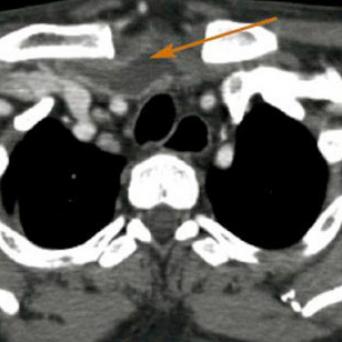

L’image

du jour